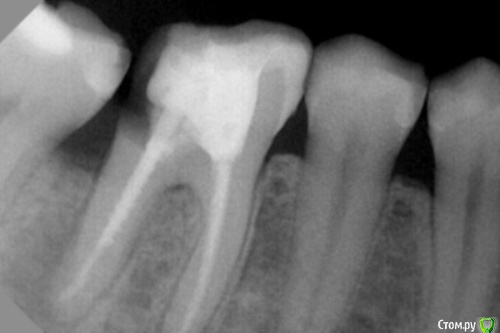

dr.Dre Опубликовано 30 ноября, 2016 Поделиться Опубликовано 30 ноября, 2016 Добрый вечер,уважаемые коллеги ,вот такая ситуация 46 зуб ноющая боль,анкер убрал еще хуже сделал 2 часа ушло,что скажете если мта закрыть какой прогноз данного зуба? Ссылка на комментарий

vse32 Опубликовано 30 ноября, 2016 Поделиться Опубликовано 30 ноября, 2016 Что Вы хотите закрывать МТА?Мне кажется, что трещина по бифуркации?В любом случае, на втором снимке после удаления штифта фатальная убыль тканей зуба в дистальной части. Протезирование, похоже там уже не вариант. Плюс киста.В общем, лечение титаном. Ссылка на комментарий

Kolchanov Опубликовано 30 ноября, 2016 Поделиться Опубликовано 30 ноября, 2016 (изменено) Из описания абсолютно не ясно где проблема. Видно только снижение плотности тканей зуба в области фуркации и дистального корня. Кстати, можно попробовать просто через окуляр микроскопа телефоном фотографировать. Мы когда учились, то на гистологии и патане удавалось препараты сфотографировать вполне сносно, а тогда телефончики были те еще. Изменено 30 ноября, 2016 пользователем Kolchanov Ссылка на комментарий

Kolchanov Опубликовано 30 ноября, 2016 Поделиться Опубликовано 30 ноября, 2016 Не знаю. Я тоже делал перфорации, но там как-то более экономные они выходили, закрывал. Фото бы помогло дать совет. На рентгенограмме выглядит подготовленным к удалению. Ссылка на комментарий